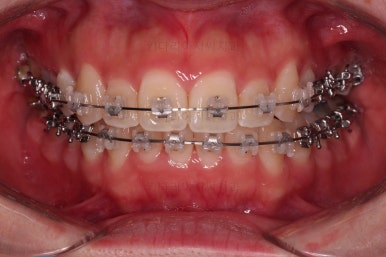

부산비대칭교정 마무리 때의 입안의 모습입니다.

가지런한 느낌은 좋지만 정중선 당연히 약간 안맞고요.

폭도 100%는 안맞아서 어금니쪽이 약간 애매한 교합이기도 했습니다.

하지만 이정도의 비대칭 상황에서 이정도의 교합은 교정만으로 할 수 있는 베스트가 아닌가 생각됩니다.